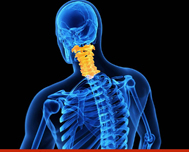

Cervical Spondilitis

Cervical Spondylosis

Spondylosis